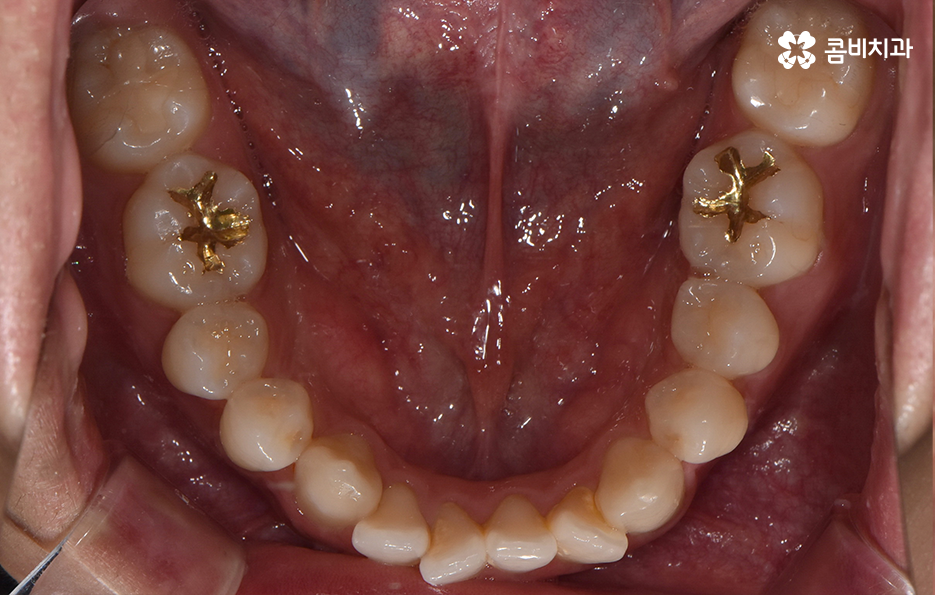

오늘 포스팅에서 보여지는 사진에서는 비발치 교정으로 덧니 교정이 가능했던 사례입니다. 덧니 교정 사례에서 발치교정 케이스는 흔한 치료 방법이긴 하지만 발치에 대한 판단은 치열만이 아니라 골격과 얼굴형을 종합적으로 고려하여 판단하고 치아를 얼마나 이동시켜야 할지 예측하여 판단하기 때문에 3D CT 등의 첨단 장비를 통한 검진과 경험 많은 교정 전문의와 충분히 상의하고 결정해야 합니다

종합하면 발치교정의 필요성은 얼굴과의 조화, 골격 그리고 교합 등을 전체적으로 고려하여 판단하기 때문에 각 환자분들이 필요한 치아의 이동 정도를 정확히 예측하고 필요한 치아 이동 공간을 확보함에 있어서 발치교정이 적합할지 아니면 비발치적인 방법으로도 치아 이동 공간이 확보 가능한지 따져보고 있으며 발치교정이 아니더라도 치간삭제, 악궁확장, 어금니 후방이동과 같은 방법으로 공간 확보가 가능하기 때문에 각 환자분들에게 적합한 1:1 맞춤형 치료가 진행되고 있어요